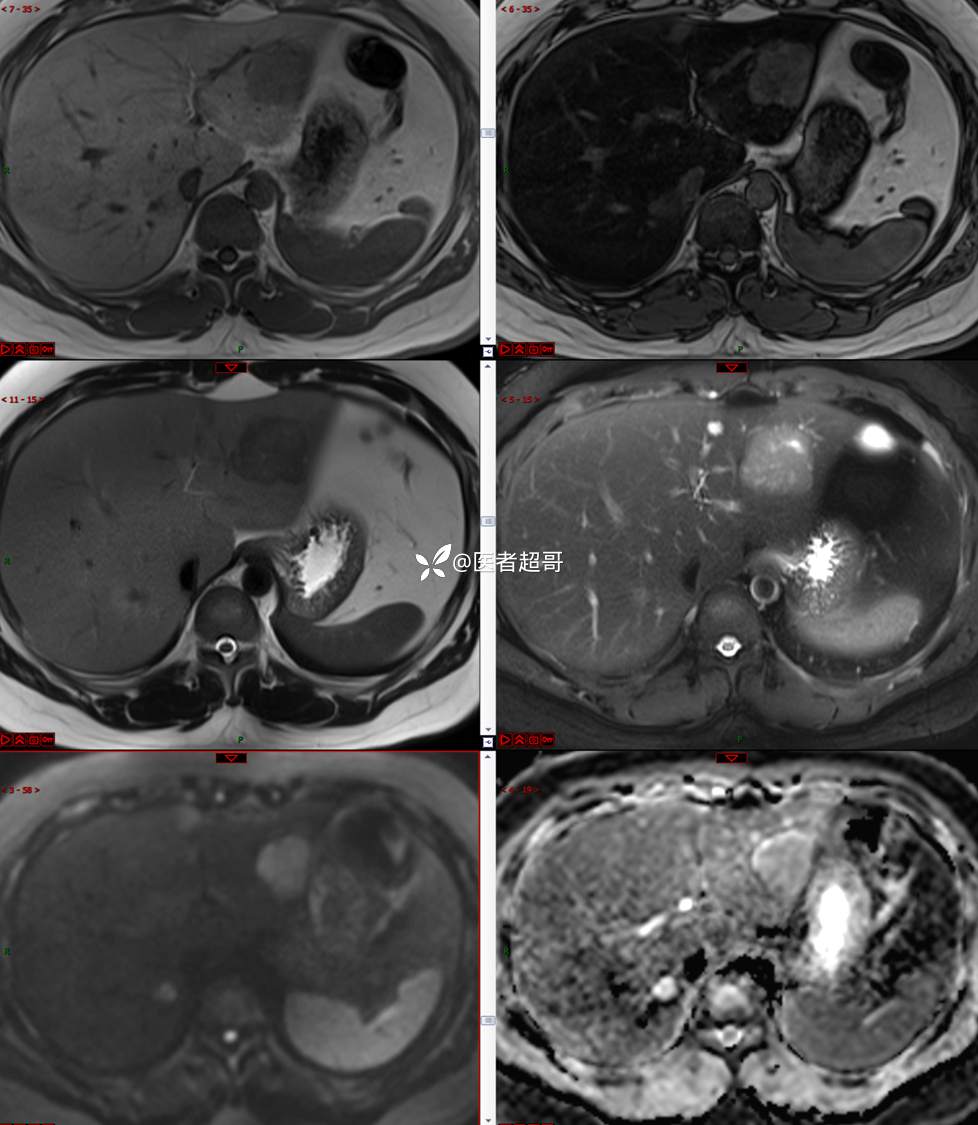

【影诊笔记800】青年男性,肝脏占位,特殊对比剂提示富血供,您能想到啥?有结果!

男,31y

主 诉:发现肝占位性病变5天。

现病史:患者缘于5天前体检时发现肝占位性病变,未予以特殊处置。现患者为求系统诊治就诊于我院,行普美显提示:肝左叶富血供占位,请结合临床及其他检查,肝多发血管瘤,脂肪肝,肝囊肿,请结合临床。门诊以“肝占位性病变”收入我科。病程中,饮食睡眠可,二便可,近期体重未见明显变化。